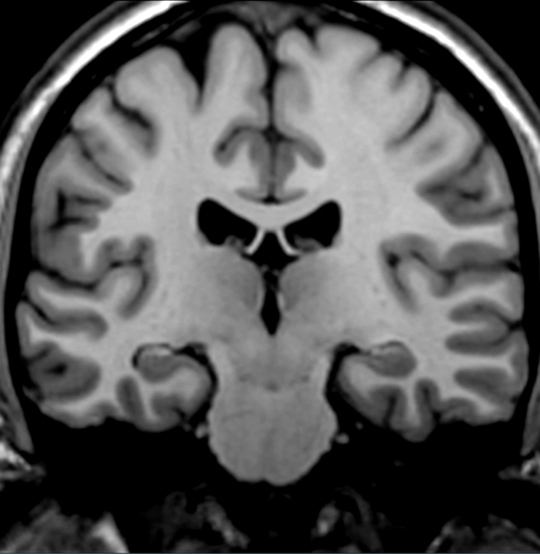

Locate the cingulate gyrus.